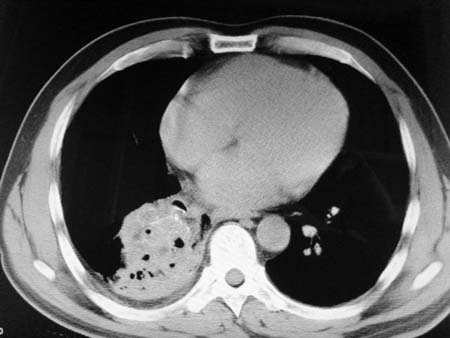

以下是引用qian在2008-4-27 17:02:00的发言:[br]考虑右下肺肺段隔离症伴有感染,建议做增强看看。

以下是引用zsl6918在2008-4-27 17:13:00的发言:[br]考虑右肺下叶炎性病变可能性大,建议抗炎治疗后复查,现有资料不能完全除外肺癌可能。